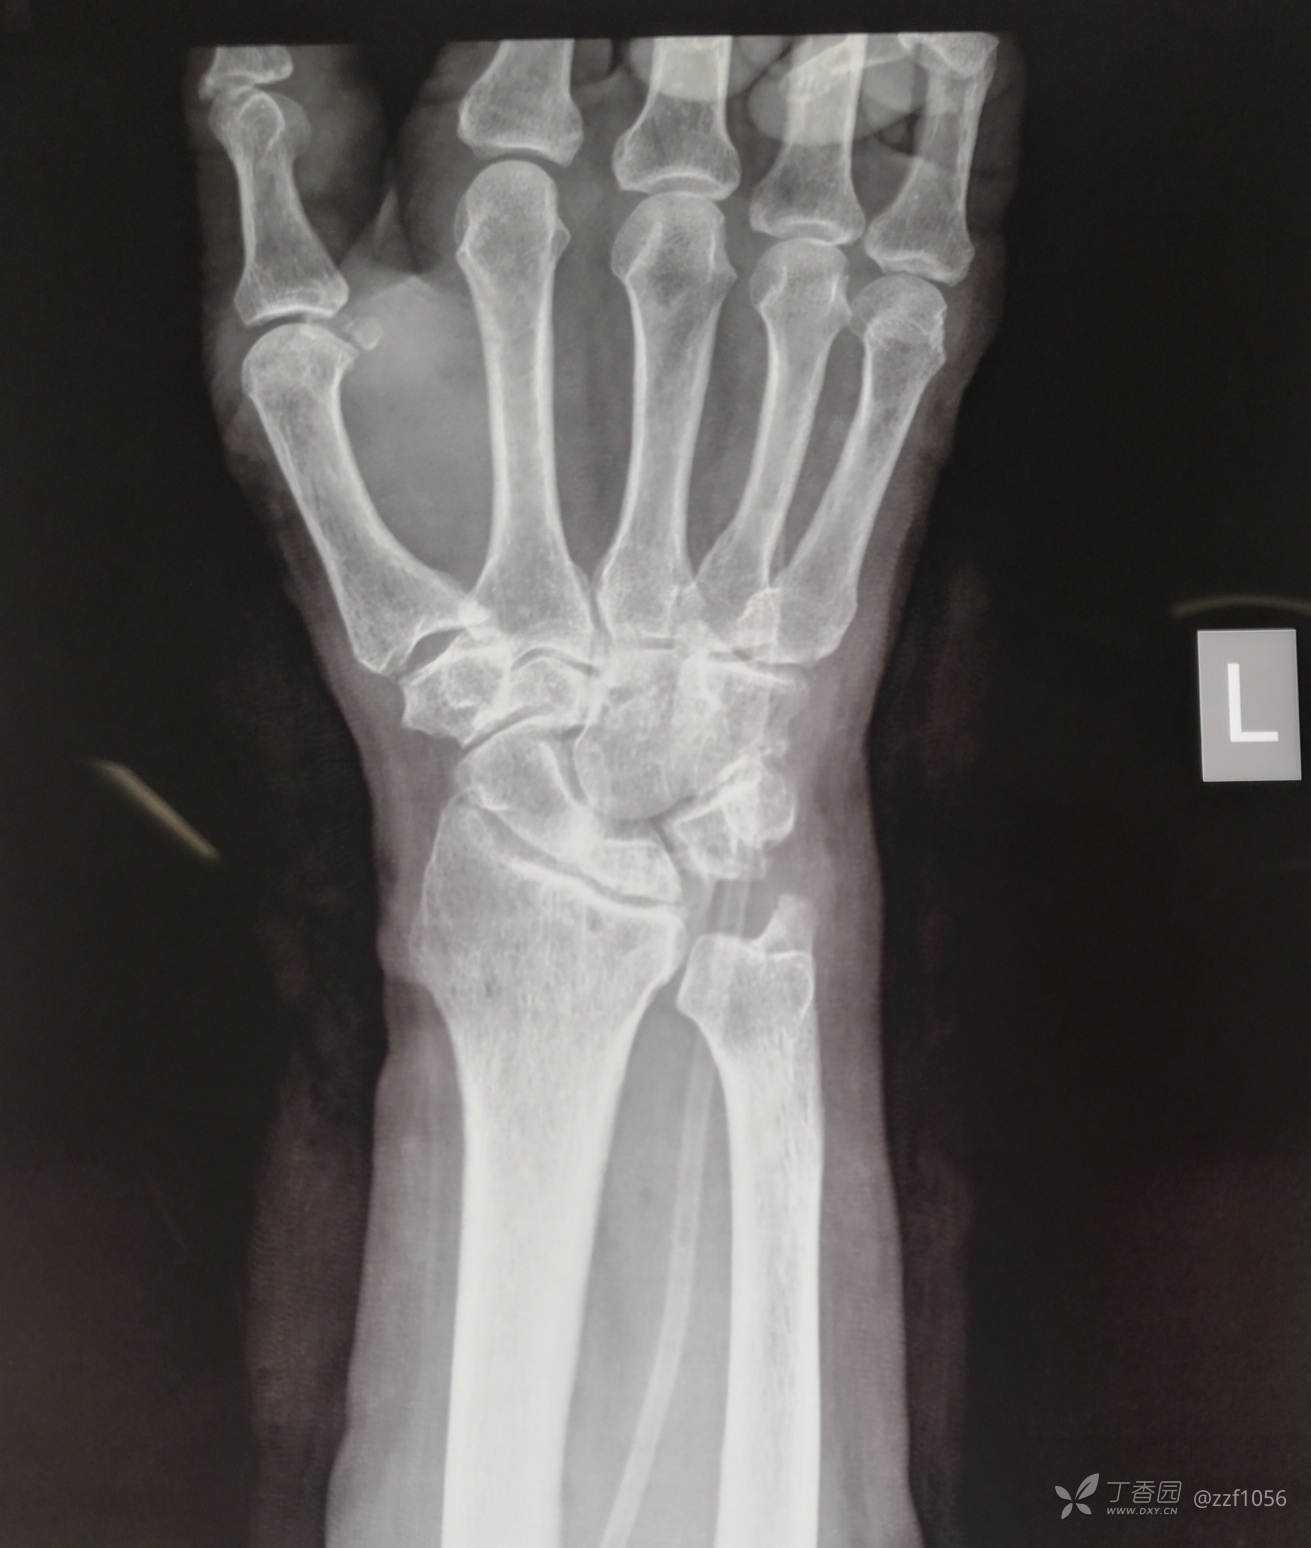

患者老年女性,68岁,左手环指伸指障碍一周。

入院诊断:1、左手环小指伸指肌腱自发断裂

2、左腕关节炎

3、左侧腕月骨陈旧损伤